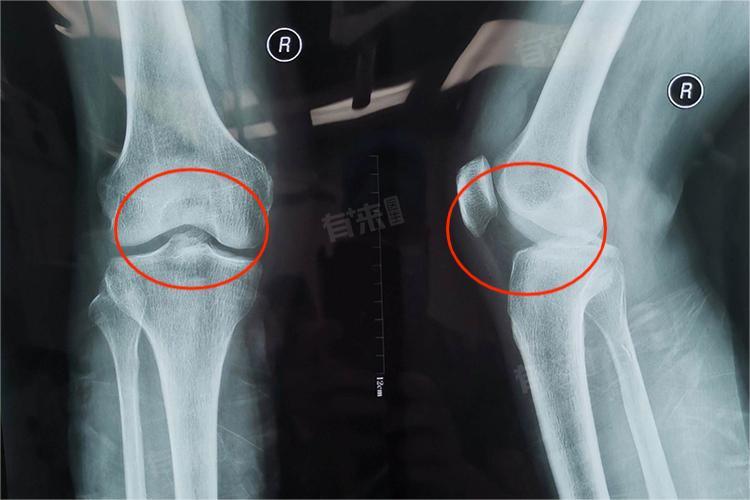

胫骨髁间棘骨折的恢复速度因骨折类型、治疗方法而异,总体而言,其恢复过程并非迅速,需要一定的时间和专业的治疗与康复。.

- 移位性或多发性骨折:移位性或多发性骨折的恢复时间更长,这类骨折往往涉及关节面的不平整,需要手术复位并内固定,以确保骨折块的对位和稳定。手术后,患者需要经历较长时间的康复期,通常在2.5-3个月,甚至更长,才能逐步恢复关节功能。

- 手术治疗:对于移位明显的骨折,手术治疗是首选。通过切开复位内固定或关节镜下手术复位,可以精确地恢复骨折块的对位和稳定。手术后,患者需要严格遵守医嘱进行康复锻炼,恢复时间通常在2-3个月,甚至更长,以确保骨折的完全愈合和关节功能的恢复。